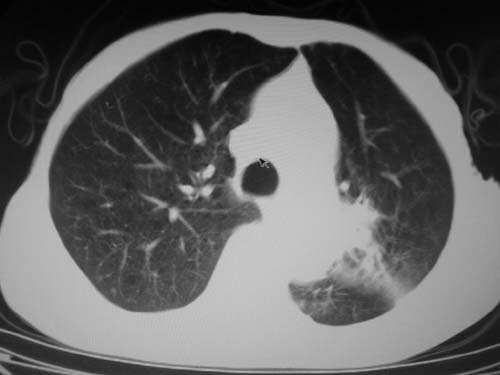

标题: CT19736:男,76岁,咳嗽,胸痛 [打印本页]

标题: CT19736:男,76岁,咳嗽,胸痛

支持左上肺周围型肺癌性并空洞形成伴胸椎转移。

左上沟癌空洞形成并胸椎转移。

考虑癌性空洞并胸椎转移。

空洞内壁有多发结节,支持癌性空洞。

支持左上肺周围型肺癌并空洞形成伴胸椎转移。z左下肺炎

左上肺癌性空洞伴胸椎转移。